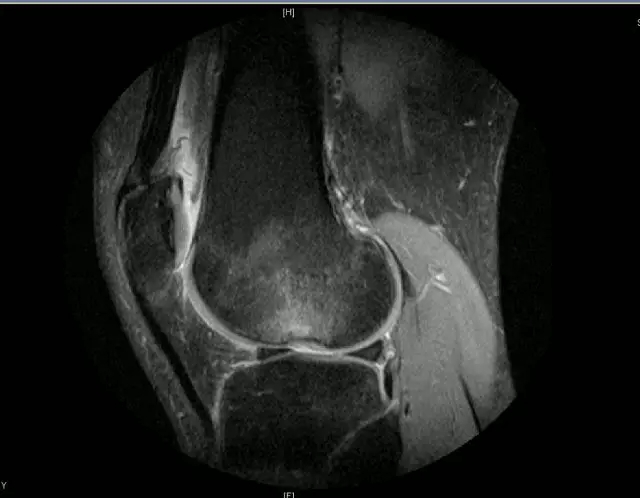

韧带结构:形态,张力,质地,连续性

半月板:完整性,形态,质地

Blumensaat 角(-1.6度)

大于9-15度视为异常

前交叉韧带与胫骨平台角度(56度)

小于45-50度视为异常

后交叉韧带折弯度

弧度:0.19厘米,角度:114-123度